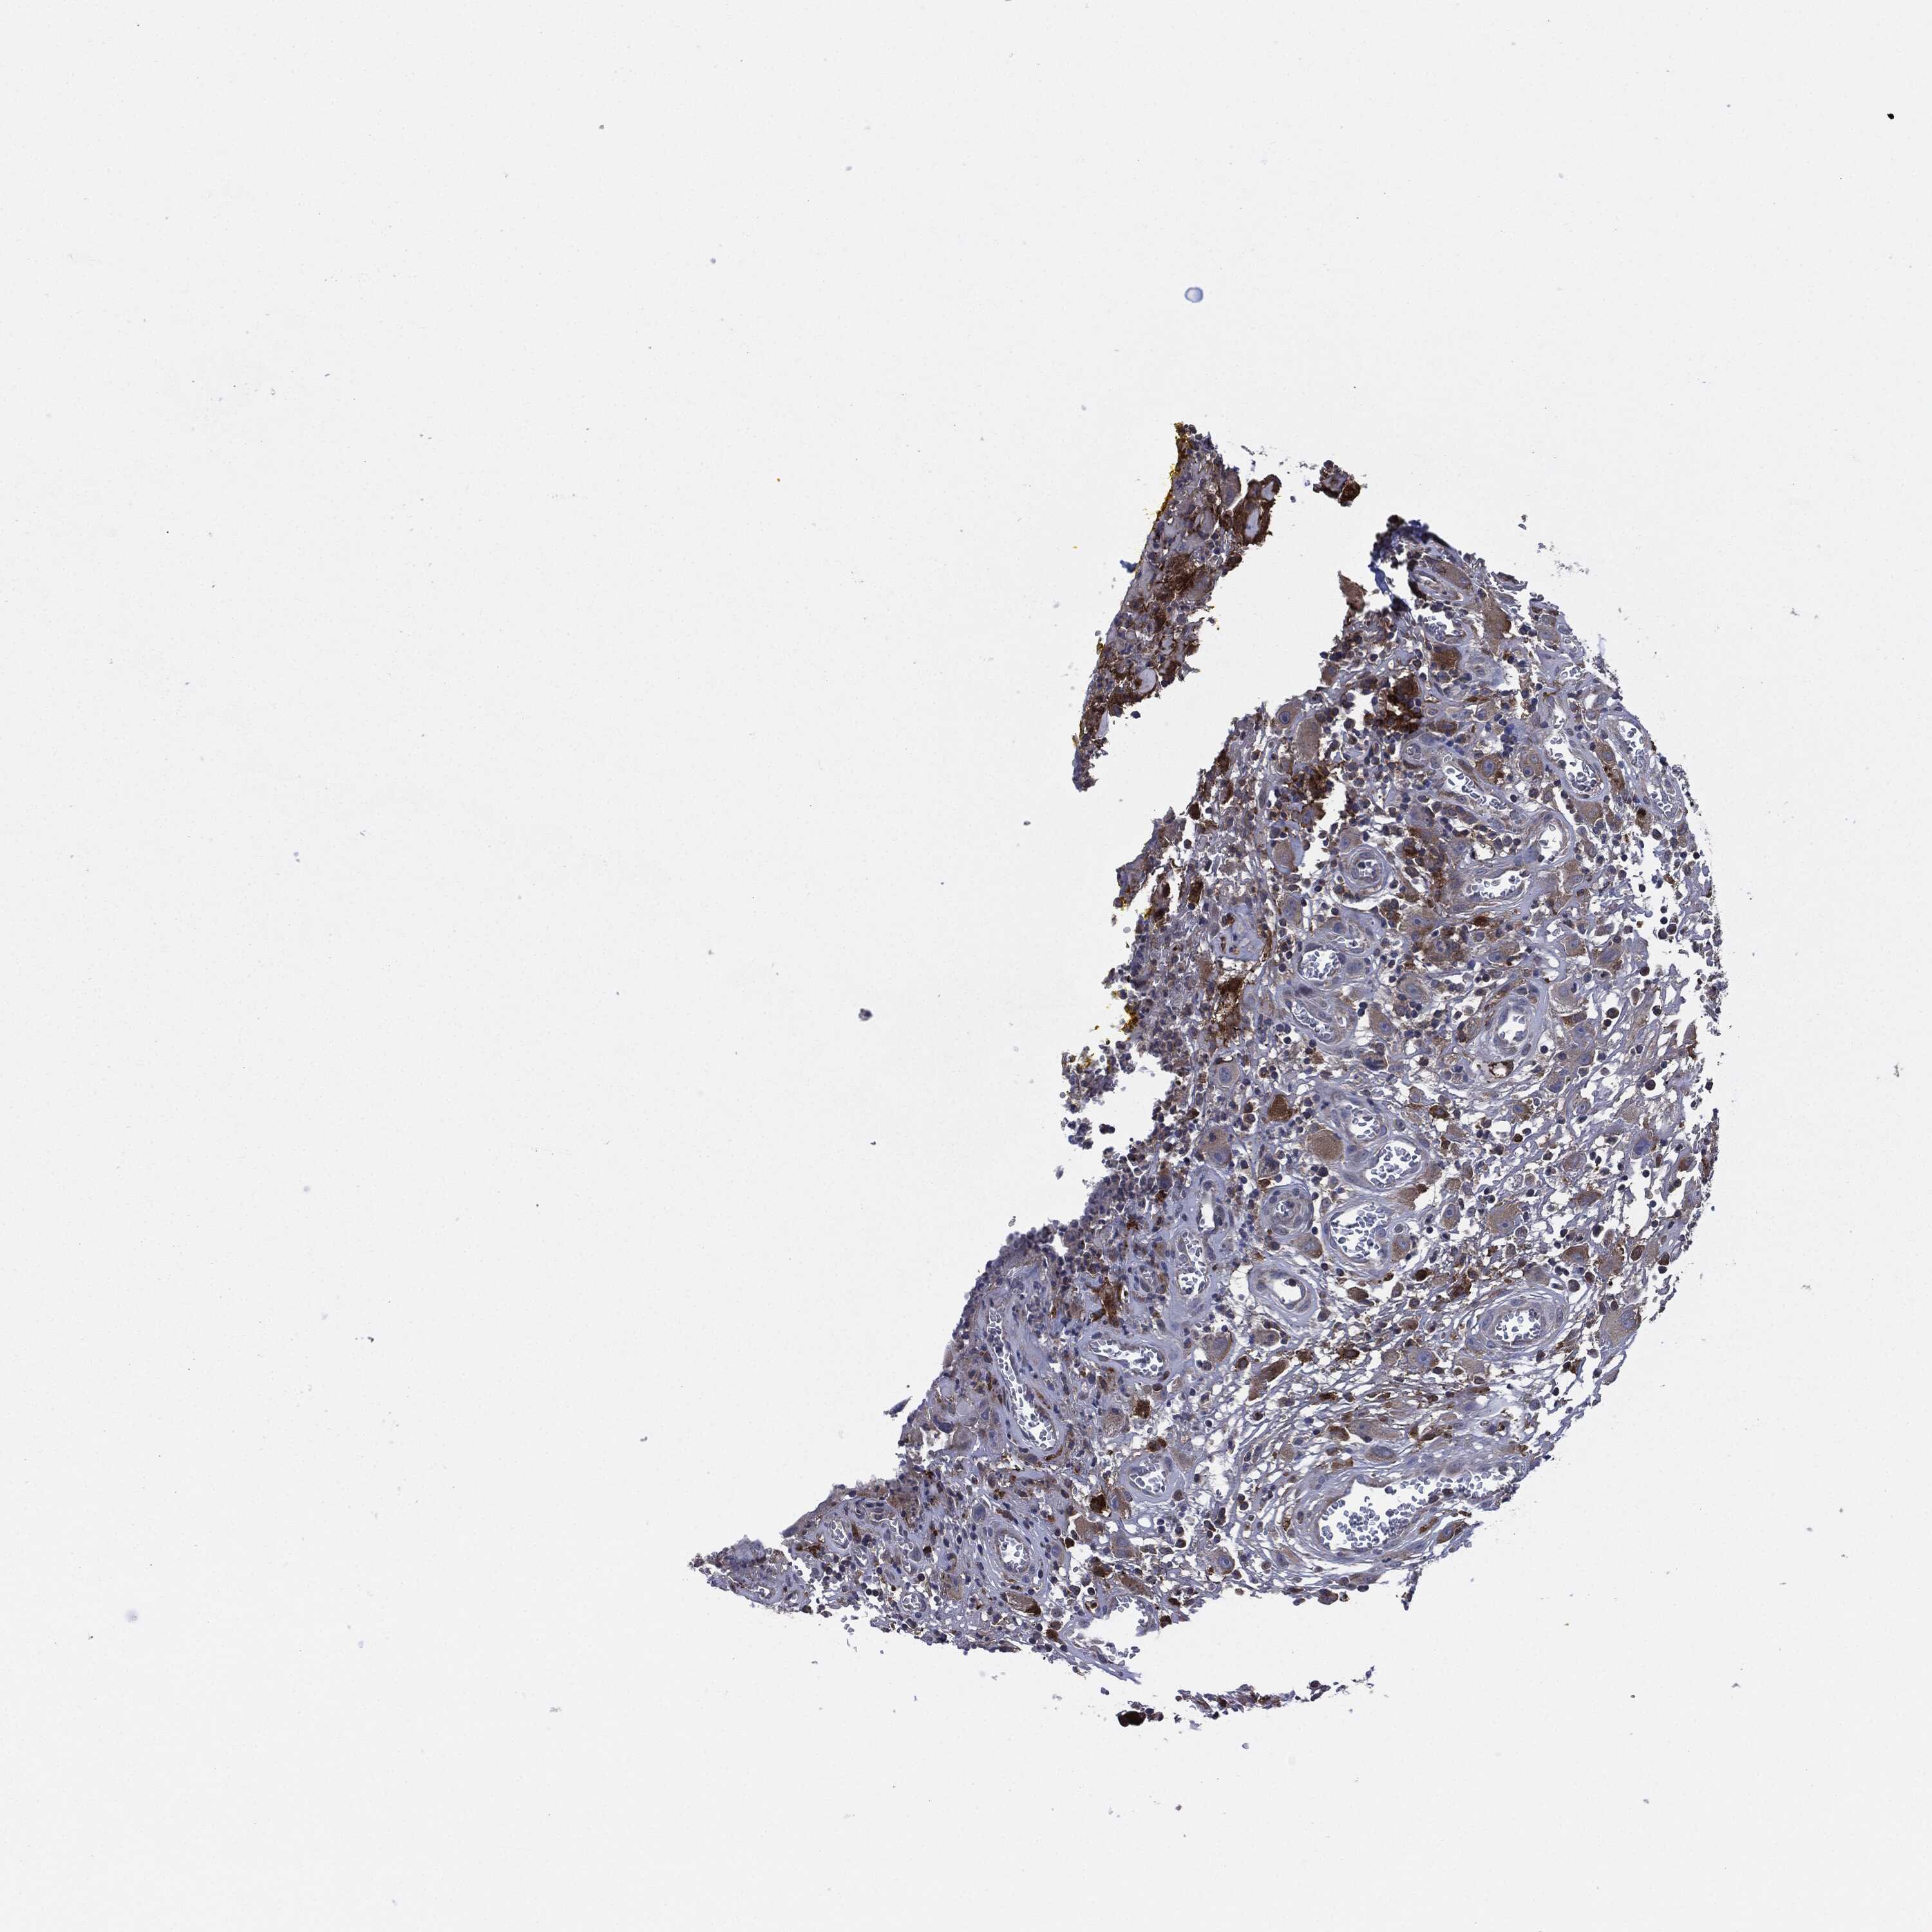

HEAD AND NECK CANCER - Protein expressioni

A mouse-over function shows sample information and annotation data. Click on an image to view it in a full screen mode. Samples can be filtered based on level of antibody staining by selecting one or several of the following categories: high, medium, low and not detected. The assay and annotation is described here.

Note that samples used for immunohistochemistry by the Human Protein Atlas do not correspond to samples in the TCGA dataset.

Antibody stainingi

Antibody staining in the annotated cell types in the current human tissue is reported as not detected, low, medium, or high, based on conventional immunohistochemistry profiling in selected tissues. This score is based on the combination of the staining intensity and fraction of stained cells.

Each image is clickable and will lead to virtual microscopy that enables deeper exploration of all samples and also displays staining intensity scores, fraction scores and subcellular localization as well as patient and tissue information for each sample.

Antibody HPA062854

Staining

High

Medium

Low

Not detected

Intensity

Strong

Moderate

Weak

Negative

Quantity

>75%

75%-25%

<25%

None

Location

Nuclear

Cytoplasmic/membranous

Cytoplasmic/membranous,nuclear

Squamous cell carcinoma, NOS

Squamous cell carcinoma, metastatic, NOS

Adenocarcinoma, NOS